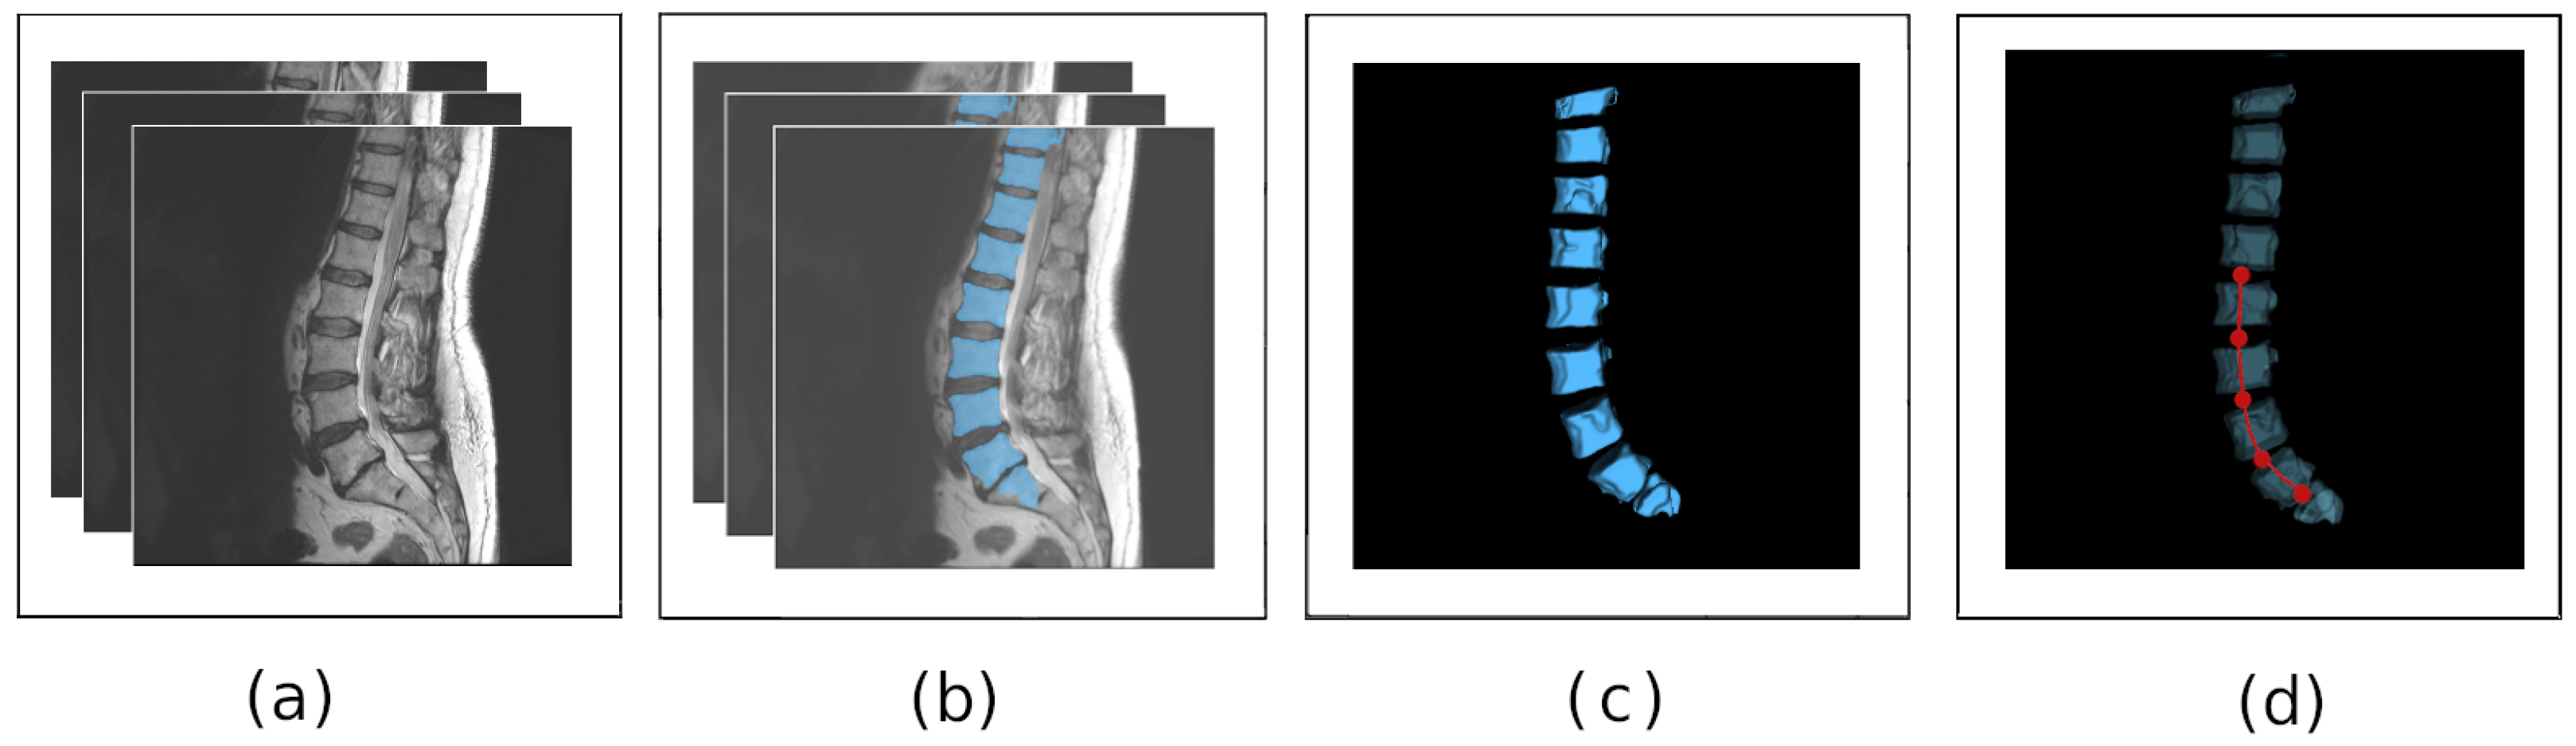

3.1. Segmentation of Vertebral Bodies from Medical Data